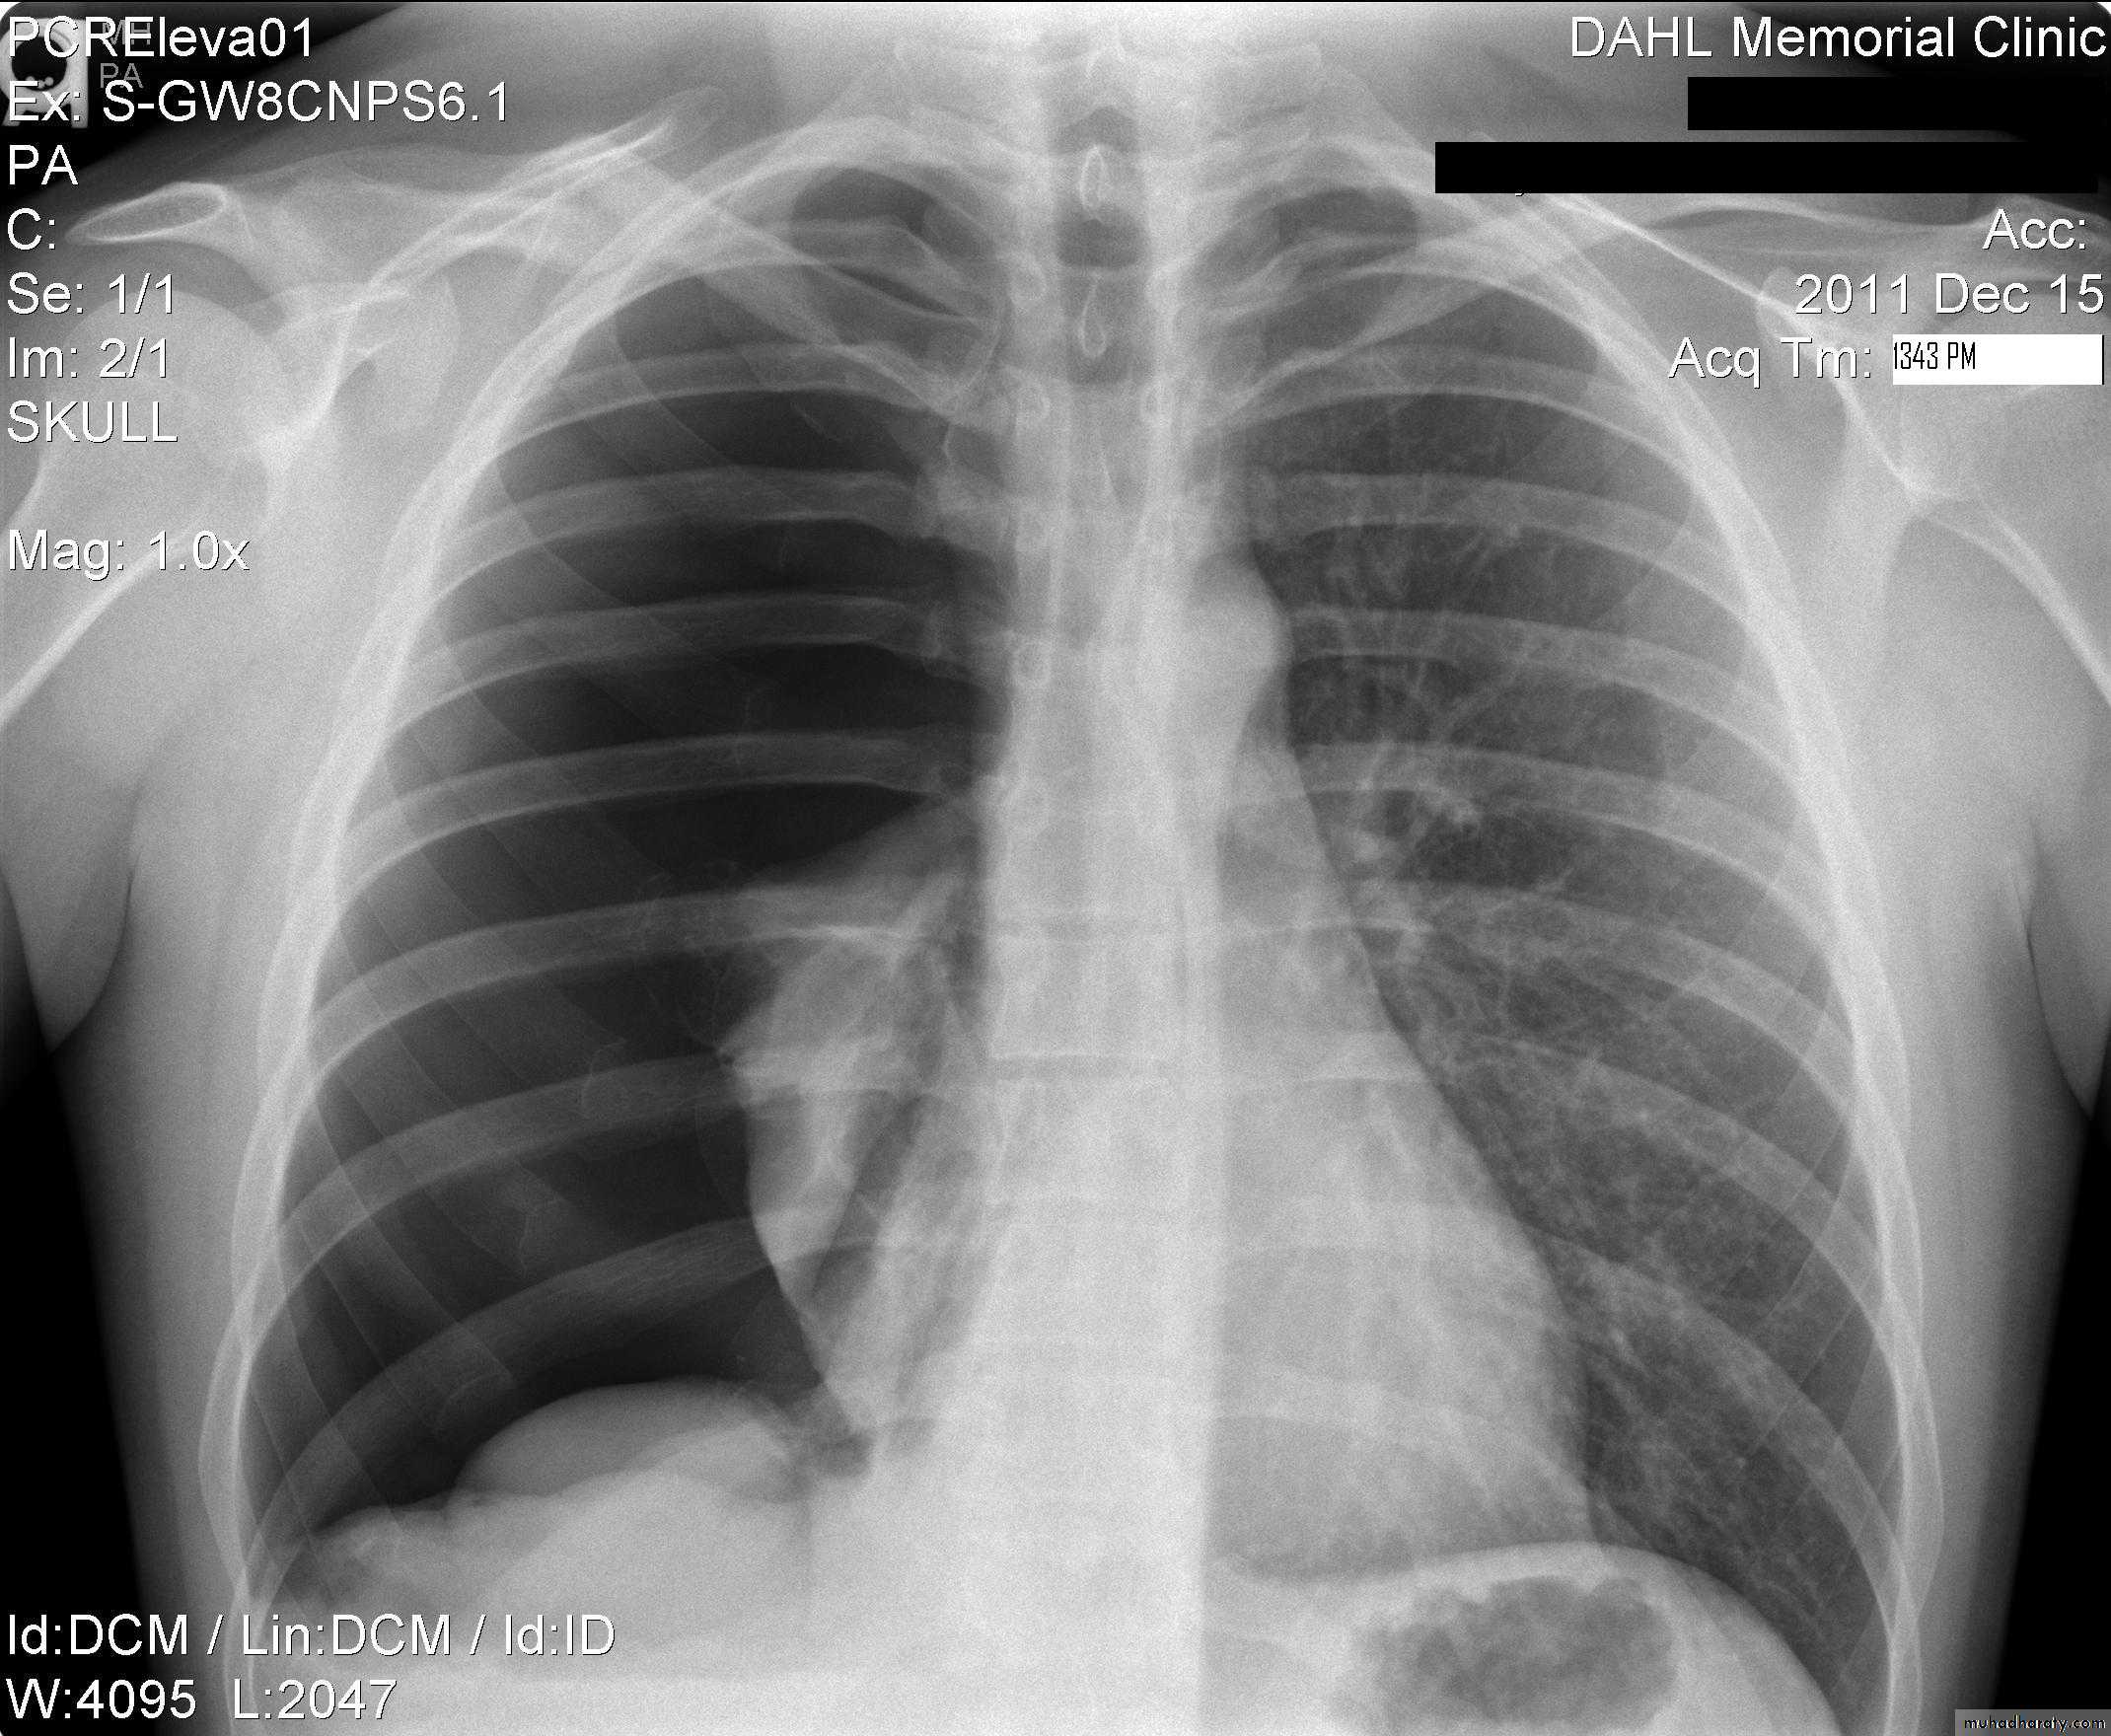

CXR of adult male PA and lateral views, it shows :Normal both lung fields ,Central cardiac shadow, Central trachea, central mediastinum, No boney lesions, no soft tissue abnormalitiesnormal radiologic anatomy of the chest Look carefully on both diaphragmatic cruse costo & cardio phrenic angles. Useful in detection of pleural effusion